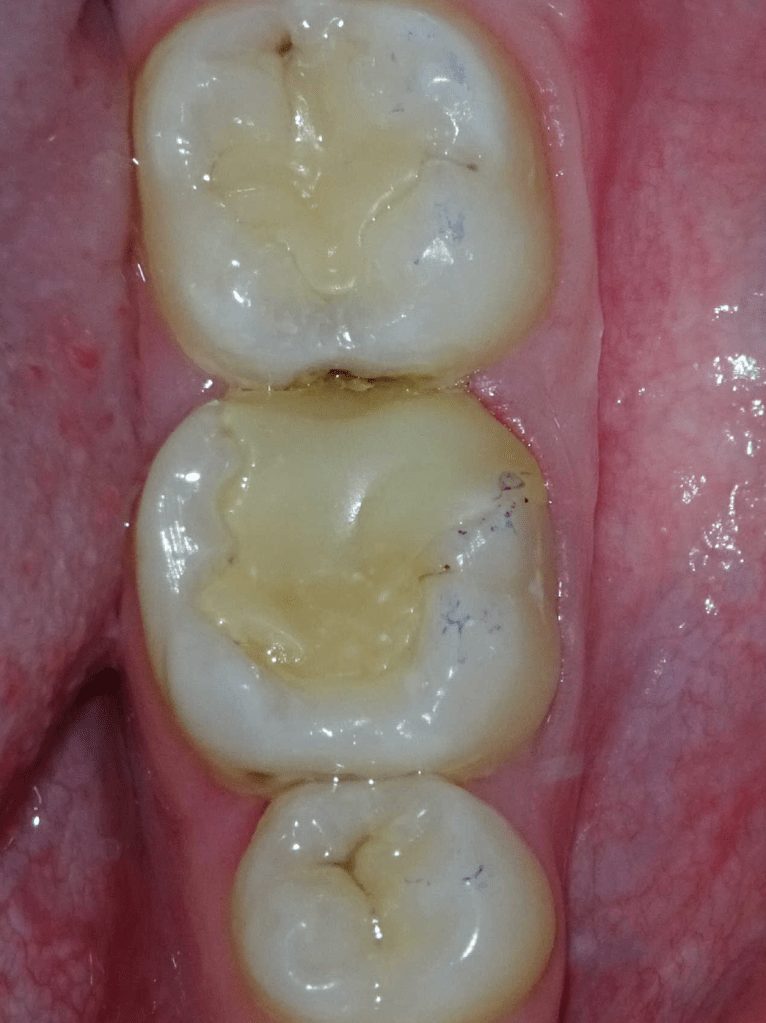

Pulpotomía biodentine + reco preendio